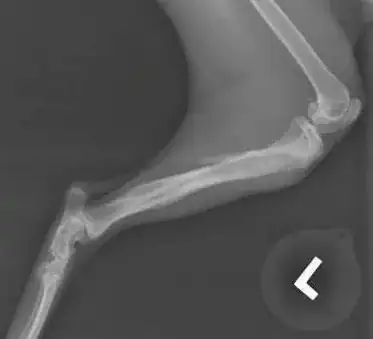

I did see a recent case which I think is quite relevant here. This is a young cat who fell off a third floor balcony, not once but twice over the course of a couple months. After the initial fall, he was limping but this seemed to resolve fairly quickly so the owner never brought him into a vet. A few months later, he had another fall, but did not seem to be getting better as quickly, and this is when I saw him. It was over a week after the second fall that he was brought in to me. These were his x-rays:

Similarly to your cat, this cat had fractures of his tibia and fibula. There are two primary fractures on the tibia. The more distal (lower) fracture shows some periosteal proliferation and callus formation, which is what happens when the body tries to heal a fracture. This is the hazy area between the fracture segments. I suspect that this is the original fracture from a couple months ago. The more proximal fracture appears more recent with no callus formation.

On his exam, the fracture did appear very stable, meaning I was unable to move the individual fracture fragments much. The cat was partially weight-bearing by this point.

I sent this cat to an orthopaedic surgeon for a second opinion and they advised to hold off on surgery for this cat, as the fractures were stable and minimally displaced. Although the x-ray looks terrible, with rest and pain management we are hopeful that this one will heal on its own. Time will tell, hoping to have a progress check on this cat in a few weeks.